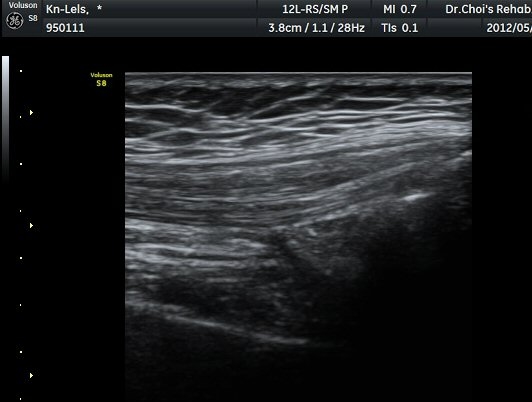

»çµÎ±Ù ÈûÁÙ Á¾´Ü¸é°Ë»ç¿¡¼­ ÈûÁÙÀÇ ºñÈİ¡ °üÂûµÈ´Ù9±×¸² 1, 2).